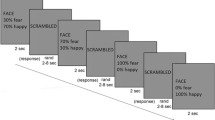

Each participant completed two visual search experiments to assess FER ability, and the process is shown in Fig. 1. In the experiments, all subjects were asked to complete the happy FER experiment first and then the fearful FER experiment. The experimental procedure is as follows. Firstly, a small white cross present at the centre of the monitor lasted 1000–2000 ms. Subsequently, two (low-load) or four (high-load) faces are presented for 600 ms, included or excluded emotional faces. Emotional faces are presented in half of the trials. It is worth mentioning that all the figures used during the experiment were selected from the Chinese Facial Affective Picture System (CFAPS)22, including thirty-two happy faces, thirty-two fearful faces and sixty-four neutral faces. The hair, ears, and face contour of all faces were excluded via Photoshop. Once faces disappear, subjects need to judge as quickly and accurately as possible ("n" if it contains an emotional face, or "m" if it does not). Next, the experimental procedure begins to cycle and the small white cross present again in the centre of the monitor. Each FER experiment contains six blocks and each block contains 40 trials. Adequate rest periods between two experiments were ensured in order to obtain the best results. Worthy of mention, all subjects were given appropriate instruction and some practice to understand the experiment beforehand.